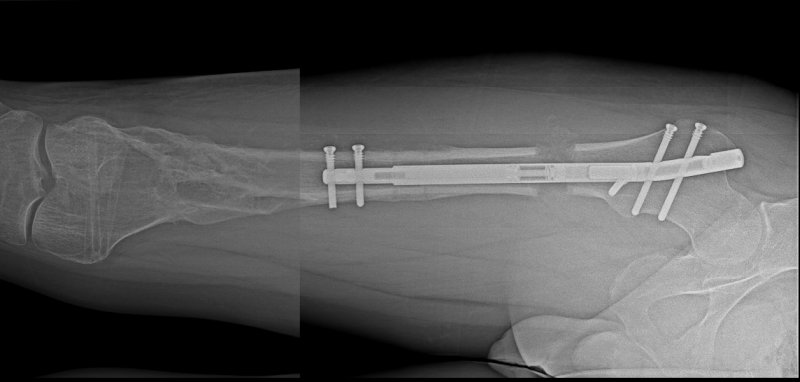

Last month, such an innovative operation was performed at Rehasport Hospital by Bartosz Musielak, MD, performing a lower limb lengthening procedure with distraction osteotomy and PRECICE magnetic nail implantation. The lower limb lengthening procedure consisted of placing a NuVasive PRECICE growing magnetic nail inside the marrow canal of the bone with a minimally invasive, percutaneous bone cut. This unique telescopic rod is equipped with a special mechanism activated by an external controller responsible for its gradual elongation.